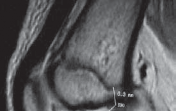

Chapter 24 Arthroscopic Drilling of Osteochondritis Dissecans Theodore J. Ganley, Gilbert Chan, and Aaron B. …